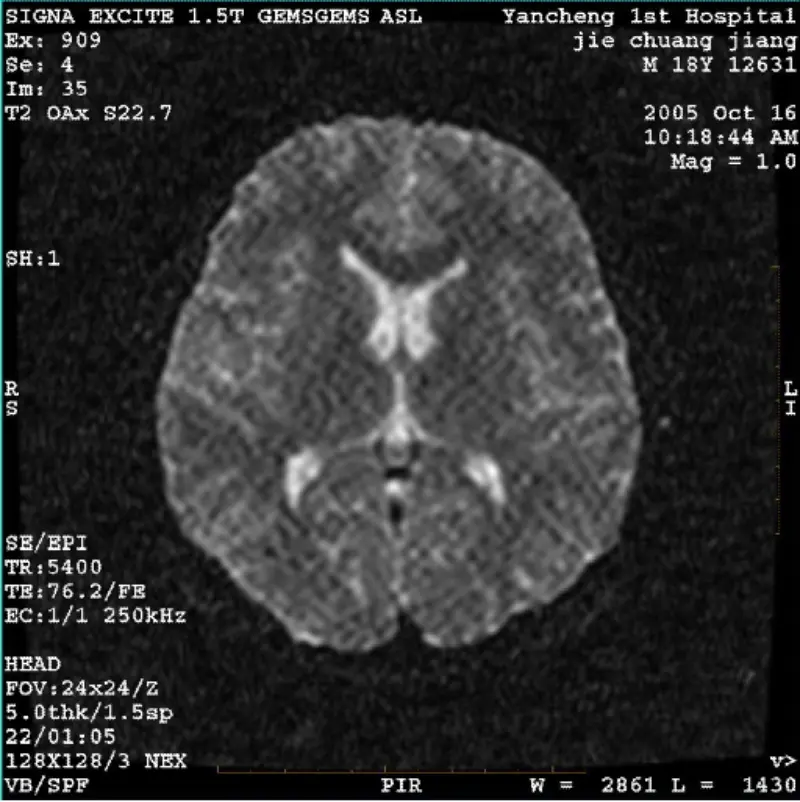

Lue lisääJÄRJESTELMÄ: 1.5T Signa Twin Excite II (ohjelmistoversio 11.0M4) ONGELMA/OIREET DWI (zoom-tila ja koko tila) ja fiesta (zoom-tila ja koko tila) kuva näkyvä verkkomainen tai vakosametti artefakti riippumatta siitä, kun käytät vartalokierrettä tai päätä kela, muu rutiinikuva näyttää normaalilta